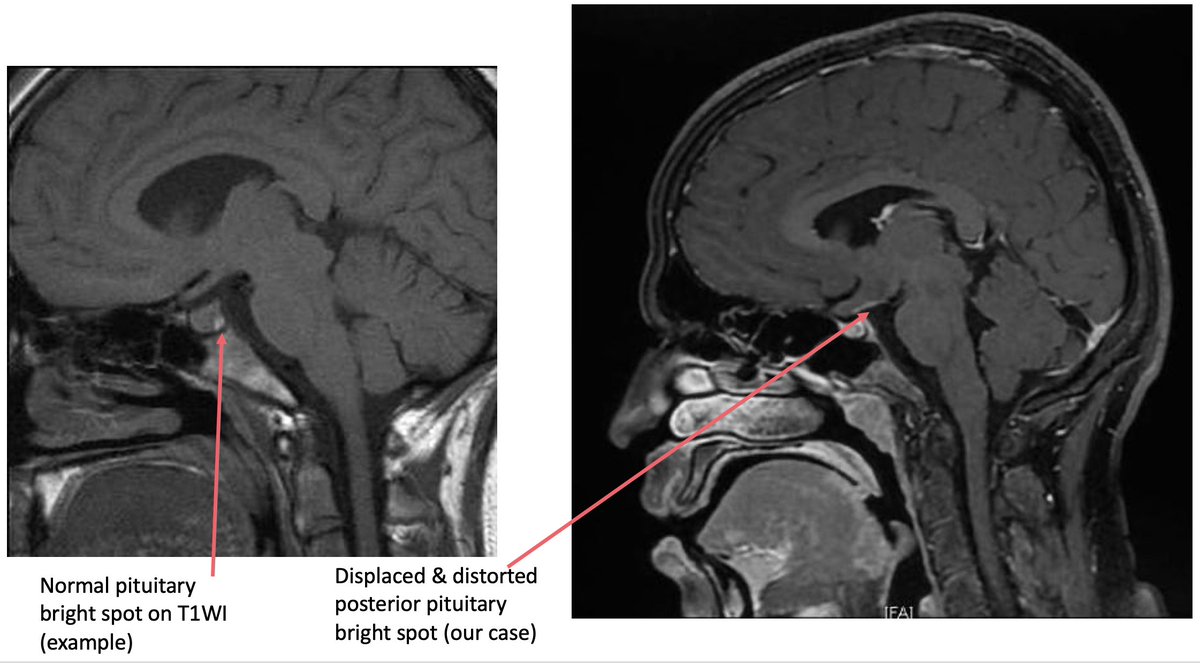

21 y/M 2018 - headache, LOW, low grade fever.Imaging had seller mass lesion for which referred to higher centre (didn't follow up). 2020 - Additiona